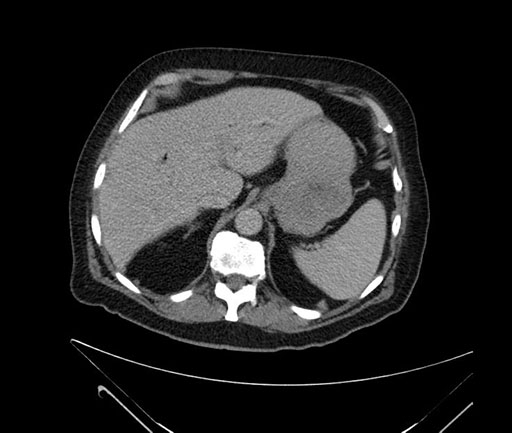

Whipple (pancreaticoduodenectomy) [case 7]

Imaging Analysis

Look through the patient's CT scan to identify any areas of concern for the necessary procedure.

Based on your CT findings, which issue(s) would give reason for "planned slowing down moment(s)" in this case?

Considering a standard Whipple procedure, what step(s) of the operation would you do differently in this case?